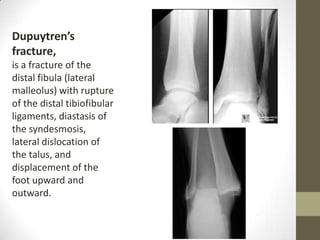

Dupuytren’s

fracture,

is a fracture of the

distal fibula (lateral

malleolus) with rupture

of the distal tibiofibular

ligaments, diastasis of

the syndesmosis,

lateral dislocation of

the talus, and

displacement of the

foot upward and

outward.

Dupuytren’s fracture

• Mechanism similar

to Maisonneuve

fracture.

• Posterior tib-fib

ligament ruptures

• Interosseous

membrane rips

• Gross diastasis